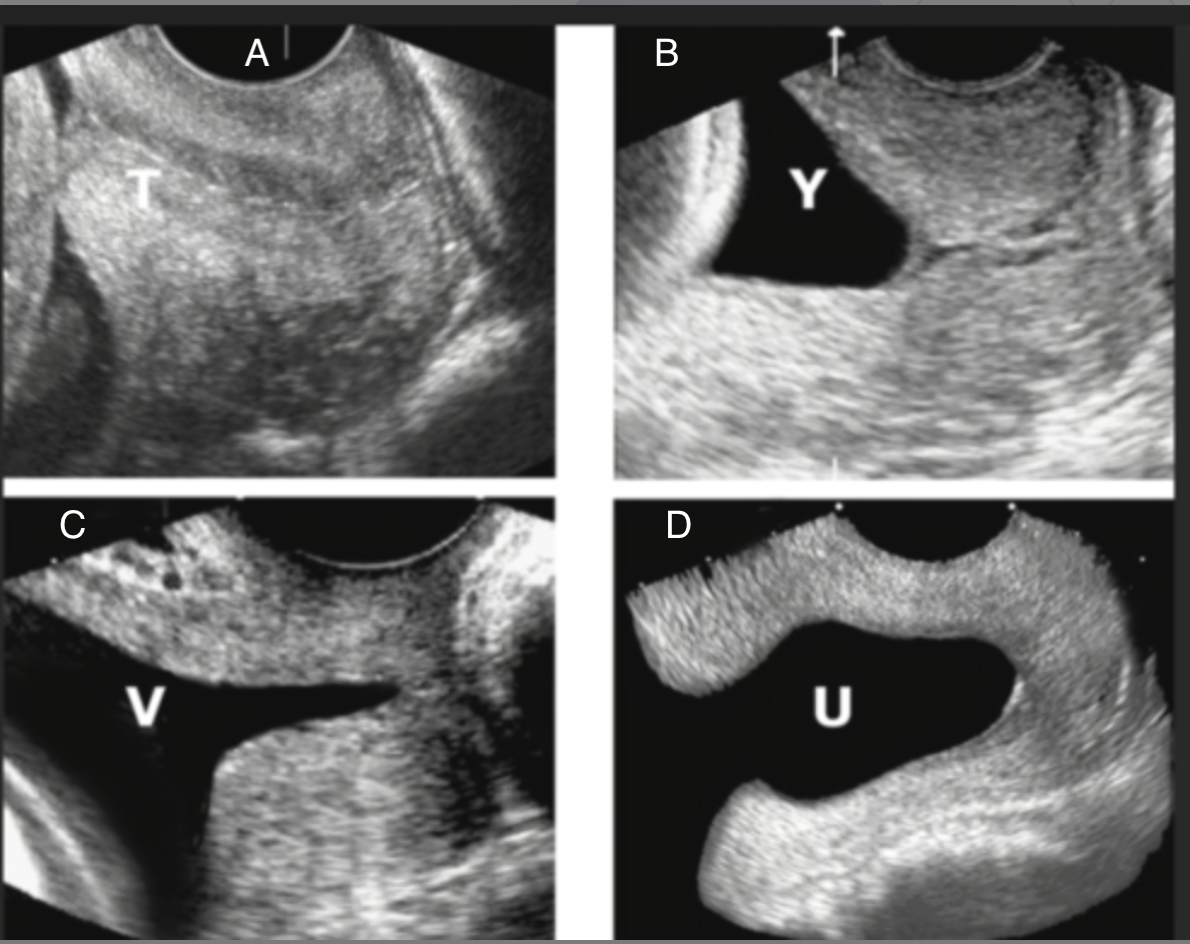

which shows funneling of the cervix

a) C + D

b) A + B

c) D only

d) B, C, D